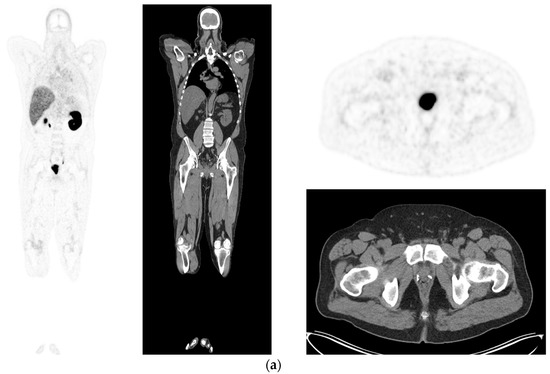

Figure 3.

Recurrent disease. 74 yr old M; radical prostatectomy 8 yrs prior; extensive para-aortic and upper pelvic lymph node involvement on CT; severe back pain; PSA 60. PSMA PET-CT: 68Ga-PSMA-216 MBq; uptake 48 min; BMI = 31.9; Wt 89 kg. (a,b): Coronal and sagittal images show bulky nodal disease with markedly increased uptake (SUV = 68.2) in abdomen and pelvis, hepatic metastases, multiple bony metastases in pelvis, lower limbs, sternum, ribs and vertebral column. (c): enlarged transaxial images of lower thorax/upper abdomen show tracer avid foci in segments 7 (SUV = 8.8), 4 (SUV = 8.7) of liver; X-hairs on lesion in right 10th rib, SUV = 14.6; CT on bone windows shows small region of sclerosis vs. extensive uptake on PET.